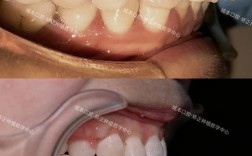

传统金属托槽矫正

- 技术描述: 使用不锈钢或金属合金制成的托槽,通过弓丝(金属丝)与托槽结扎固定,施加力量移动牙齿,这是最经典、应用最广泛的技术。